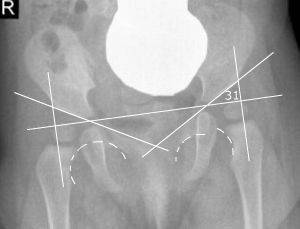

Рентген тазобедренного сустава — важнейший этап в диагностике травмы

Более точный диагноз сможет поставить только врач, который будет опираться на рентгеновский снимок. Определив степень повреждения, травматолог наложит повязку, правильно фиксирующую сустав.